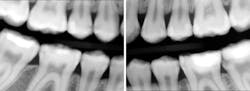

Sydney came in like clockwork every six months for recall. And at every recall appointment, she left with a treatment plan for restorative dentistry. I would start with the upper-right quadrant and work my way through over several weeks after each recall visit. After a couple of years of this, the cycle of rerestoration came full circle, and it was time for me to begin rerestoring teeth that I had worked on before. It was the same story for each restoration: recurrent decay interproximally at the gingival margin and a high plaque index, especially around the resins. At first, I took this poorly. I thought I must have sloppily placed those restorations before. I restored them again—this time bigger—with a rubber dam and moved on.

Always pleasant, Sydney would insist that she was brushing three to four times a day, flossing morning and night with string floss, and using interproximal brushes after lunch. Despite all of this, Sydney had a hard time controlling plaque, especially around the existing resin restorations. We worked with Sydney on technique. We worked with Sydney on products, and she began using a 5000-ppm sodium fluoride dentifrice, xylitol gum, and rinses. Sydney got a Sonicare. Sydney kept getting decay.